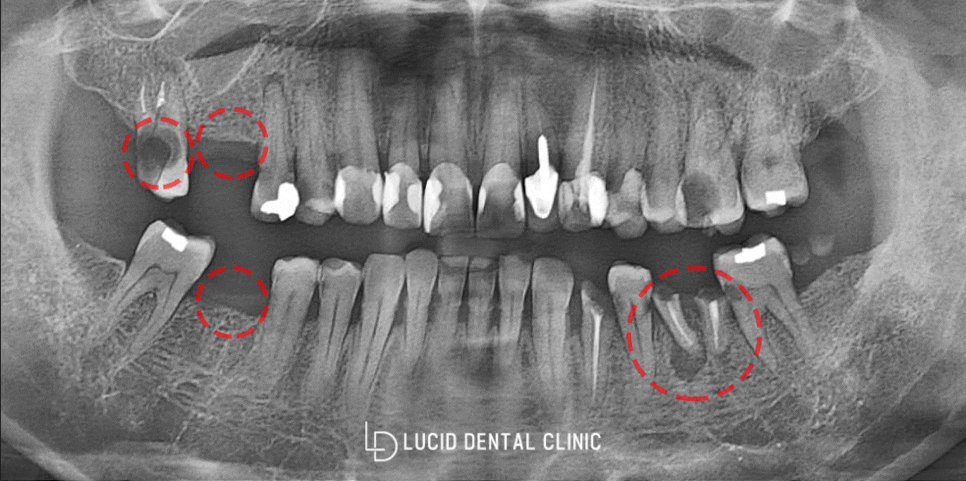

신논현역 치과 에 처음 오셨을 당시

파노라마 촬영을 통하여

구강 내 상태를 정밀히 확인했습니다.

표시된 곳 외에 두 곳 더

치료 받아야 될 것이 있는데,

우선 오늘은 임플란트를 먼저 심어드린

사례부터 소개해드리려 합니다.

윗 어금니 16, 17번,

아래 어금니 36, 46번을

보철 수술을 진행할텐데요.

16, 46을보면 아예 이가 없습니다.

이미 예전에 떨어져 나간 것으로

빈자리만 공허하게 남아있죠.

다음은 윗 어금니 17번인데요.

치수 쪽으로 감염되었을 정도로

이가 광범위하게 썩은 것을 볼 수 있었습니다.

해당 이는 아예 되살릴 수 없을만큼

썩어버려 기능을 상실했기에

발치 후 임플란트 수술을 받기로 했습니다.

마지막으로 36번 아래 어금니인데요.

잘 보시면 치관(머리)는 날라갔고,

뿌리만 남아있는 것을 확인할 수 있습니다.

게다가 뿌리 끝에 염증이 발생한 것을 볼 수 있는데요.

이는 그대로 두게 되었다가

옆에 있는 치아에 염증이 확산될 가능성이 높으며,

제 기능을 더는 할 수 없는 상황이라

신논현역 치과 에서는

얼른 발치 후 염증 치료 및 수술을 받는게 좋다

그렇게 말씀드렸습니다.